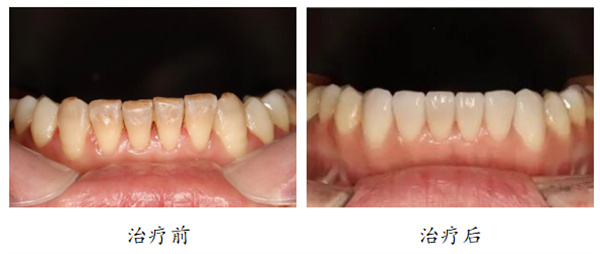

2、变色牙

“我的牙齿上有去不掉的斑点,怎么办呢?”

“有些朋友因为四环素牙、氟斑牙等等原因,导致牙齿的颜色不好看,或者是牙齿上有一些纹路和斑点,这时候就可以选择牙贴面,在牙齿的表面来贴一层瓷来掩盖啦。”